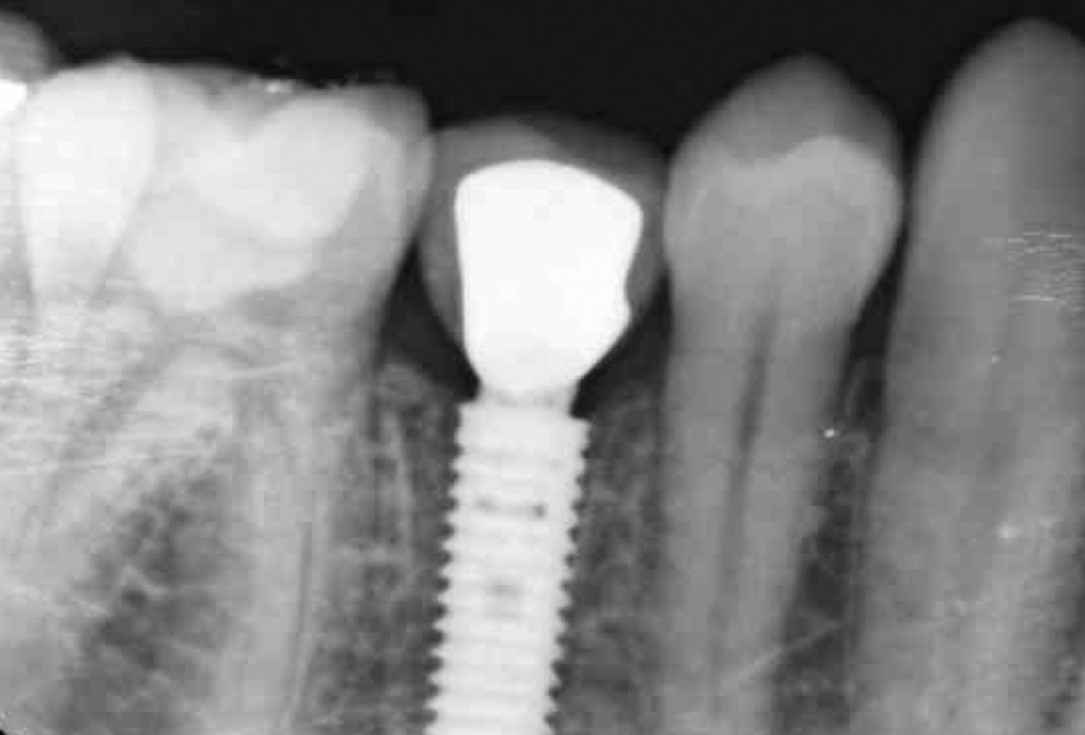

17/17 - X-ray at 2 years presenting stable hard tissuesApplication of mucoderm® for soft tissue management around single implants at second stage surgery Dr. C. De Annuntiis